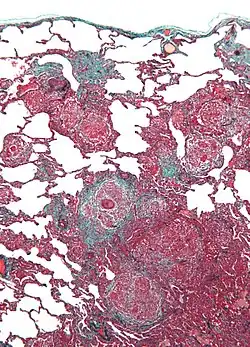

| Micrograph of hypersensitivity pneumonitis, the histologic correlate of bird fancier's lung. Lung biopsy. Trichrome stain. | |

Bird fancier's lung (BFL), also known as bird breeder's lung or pigeon lung, is a type of hypersensitivity pneumonitis. It can cause shortness of breath, fever, dry cough, chest pain, anorexia and weight loss, fatigue, and progressive pulmonary fibrosis (the most serious complication). It is triggered by exposure to avian proteins present in the dry dust of droppings or feathers of a variety of birds. The lungs become inflamed, with granuloma formation. It mostly affects people who work with birds or own many birds.

BFL causes inflammation of the alveoli in the lungs. Avian proteins include mucins and antibodies, which stimulate a significant immune response from the body.[3] The lungs become inflamed, with granuloma formation. It can take many years of exposure to cause BFL, with an average of 1.6 years to cause acute disease, and 16 years to cause chronic disease.[2]

Lung biopsy usually reveals non-necrotizing granulomatous inflammation.[7] It also shows "foamy" macrophages and crystals of oxalic acid.[3] Hyperplasia tends to occur in type 1 pneumocytes and not in type 2 pneumocytes.[3]